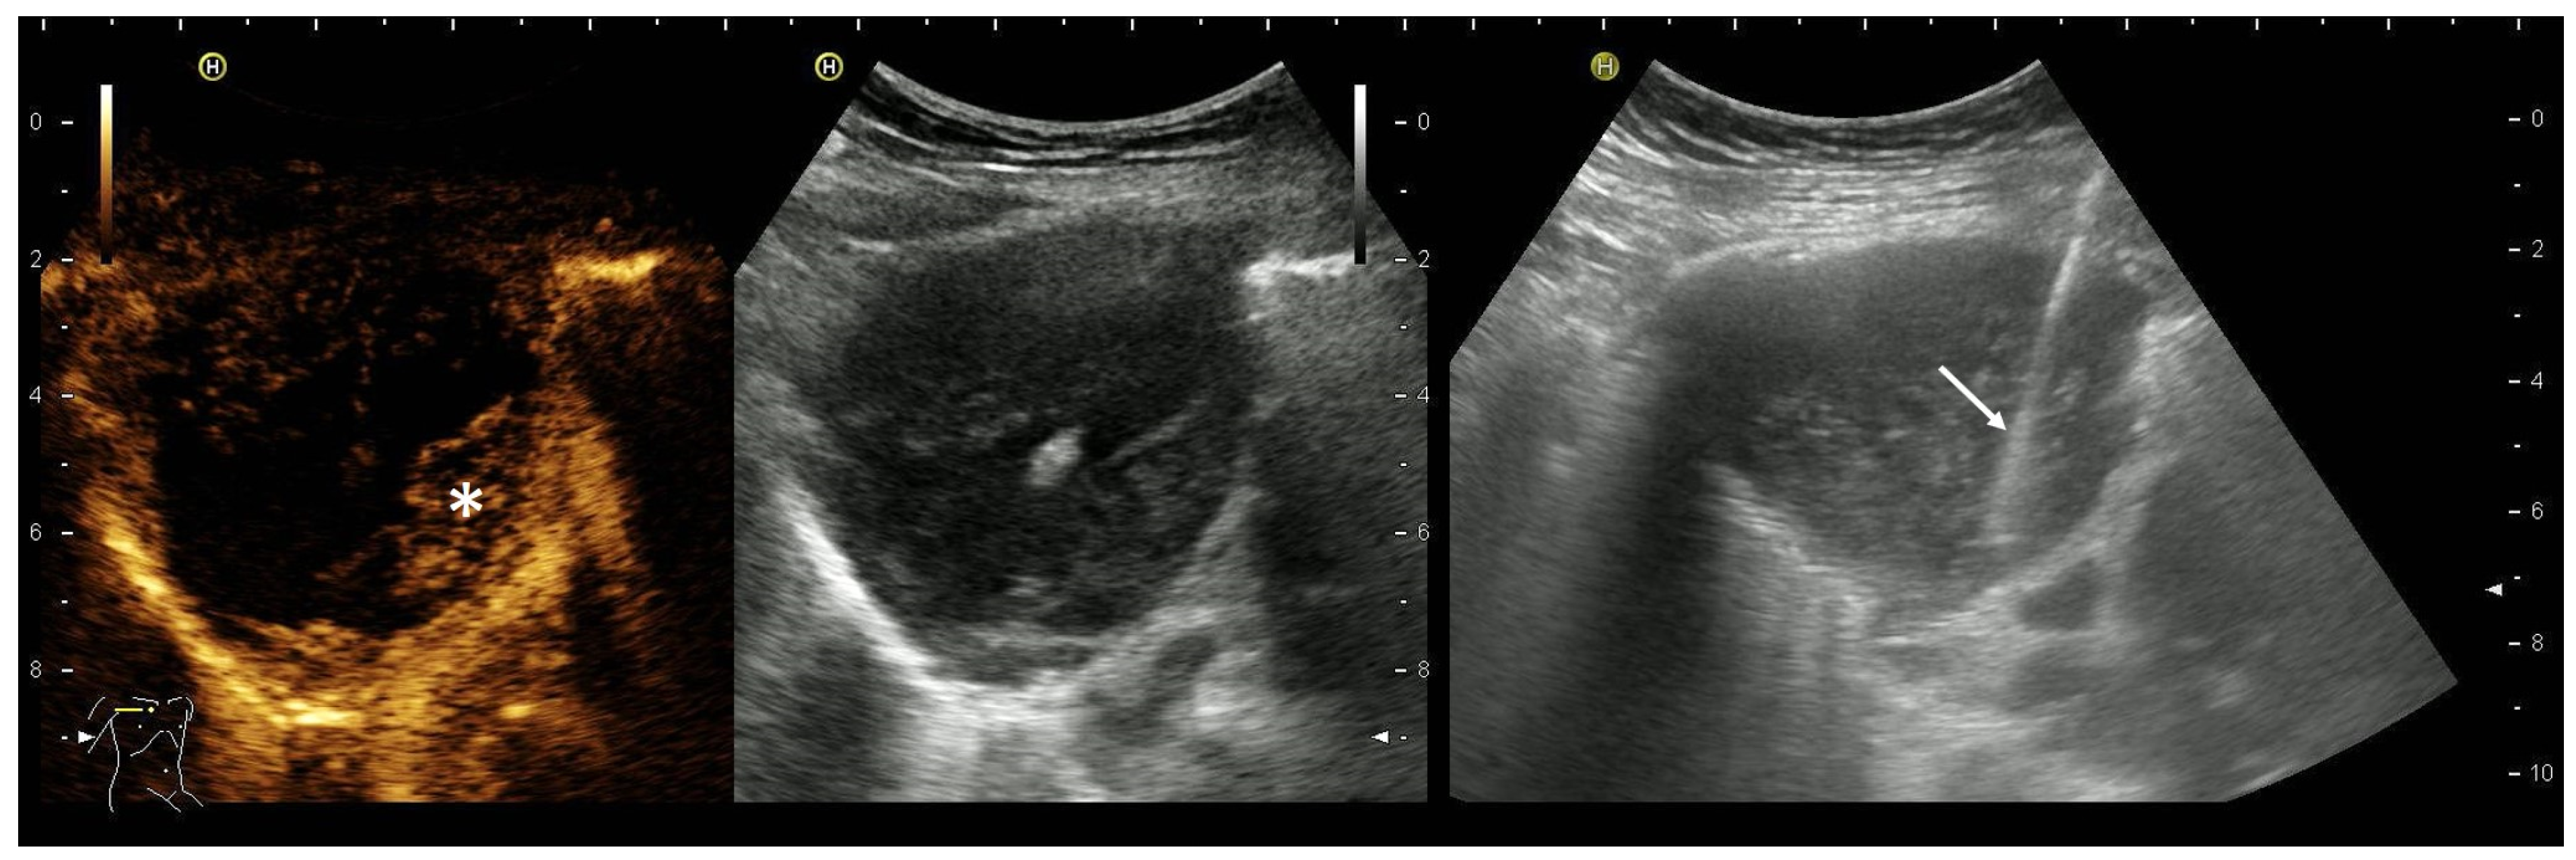

2. Primary Pulmonary Sarcomas